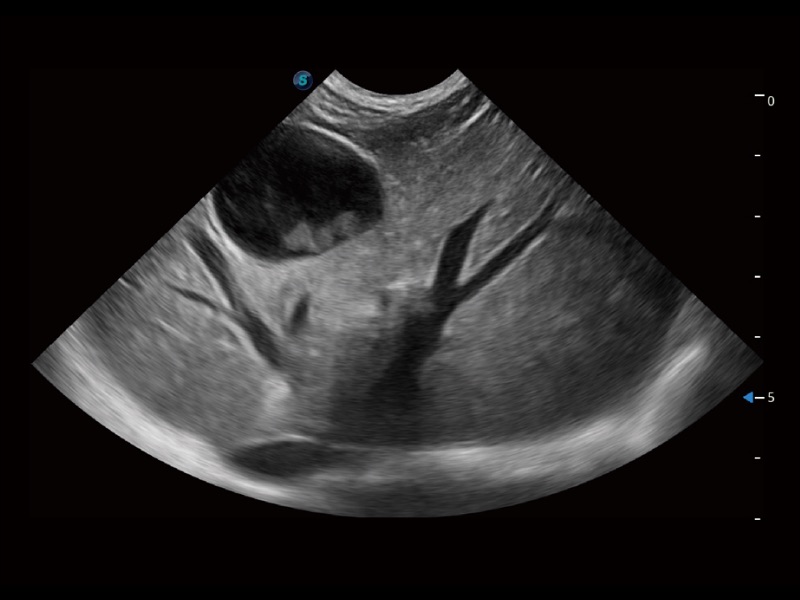

通過色彩血流和實(shí)時(shí)寬景相結(jié)合,可觀察到完整的靜脈或動脈的血流,方便醫(yī)生檢查。實(shí)時(shí)掃查過程中,如有任何操作失誤也可以很容易地進(jìn)行回掃擦除,而不會中斷掃查。

為精細(xì)結(jié)構(gòu)及組織邊緣提供高清晰度的圖像和更大的成像視野。幫助減輕醫(yī)生的用眼疲勞,快速精準(zhǔn)獲得測量的數(shù)據(jù)。

ProPet 70 全新的動物超聲智能軟件和豐富的探頭群,為動物醫(yī)生提供了高清晰度和精細(xì)分辨率的圖像,無論在寵物、馬科、畜牧還是實(shí)驗(yàn)室動物等應(yīng)用中都可以輕松應(yīng)對,為您的日常工作帶來滿意的體驗(yàn)。